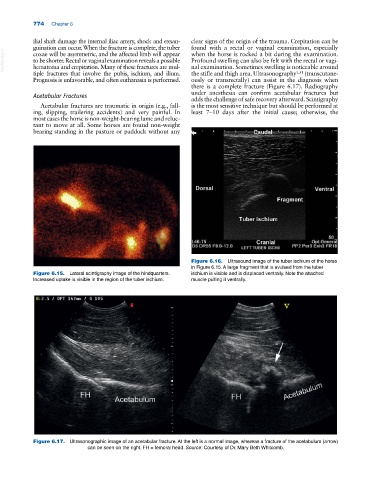

Figure 6.16. Ultrasound image of the tuber ischium of the horse

in Figure 6.15. A large fragment that is avulsed from the tuber

Figure 6.15. Lateral scintigraphy image of the hindquarters. ischium is visible and is displaced ventrally. Note the attached

Increased uptake is visible in the region of the tuber ischium. muscle pulling it ventrally.

Figure 6.17. Ultrasonographic image of an acetabular fracture. At the left is a normal image, whereas a fracture of the acetabulum (arrow)

can be seen on the right. FH = femoral head. Source: Courtesy of Dr. Mary Beth Whitcomb.